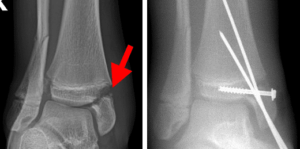

In children and adolescents, ankle fractures typically affect the tibia or fibula, often involving the growth plates—specialized areas of cartilage near the ends of long bones. Growth plates play a critical role in bone development, gradually hardening into solid bone as the child matures. However, because these growth plates are the last parts of the bones to solidify, they are particularly prone to injury and fractures. As adolescents approach the end of their growth phase, growth plates begin to close and harden, making them susceptible to transitional fractures during this maturing stage. Two common types of transitional ankle fractures are triplane fractures and Tillaux fractures, which require specific treatment approaches depending on their severity and location (refer to the Treatment section for more details)